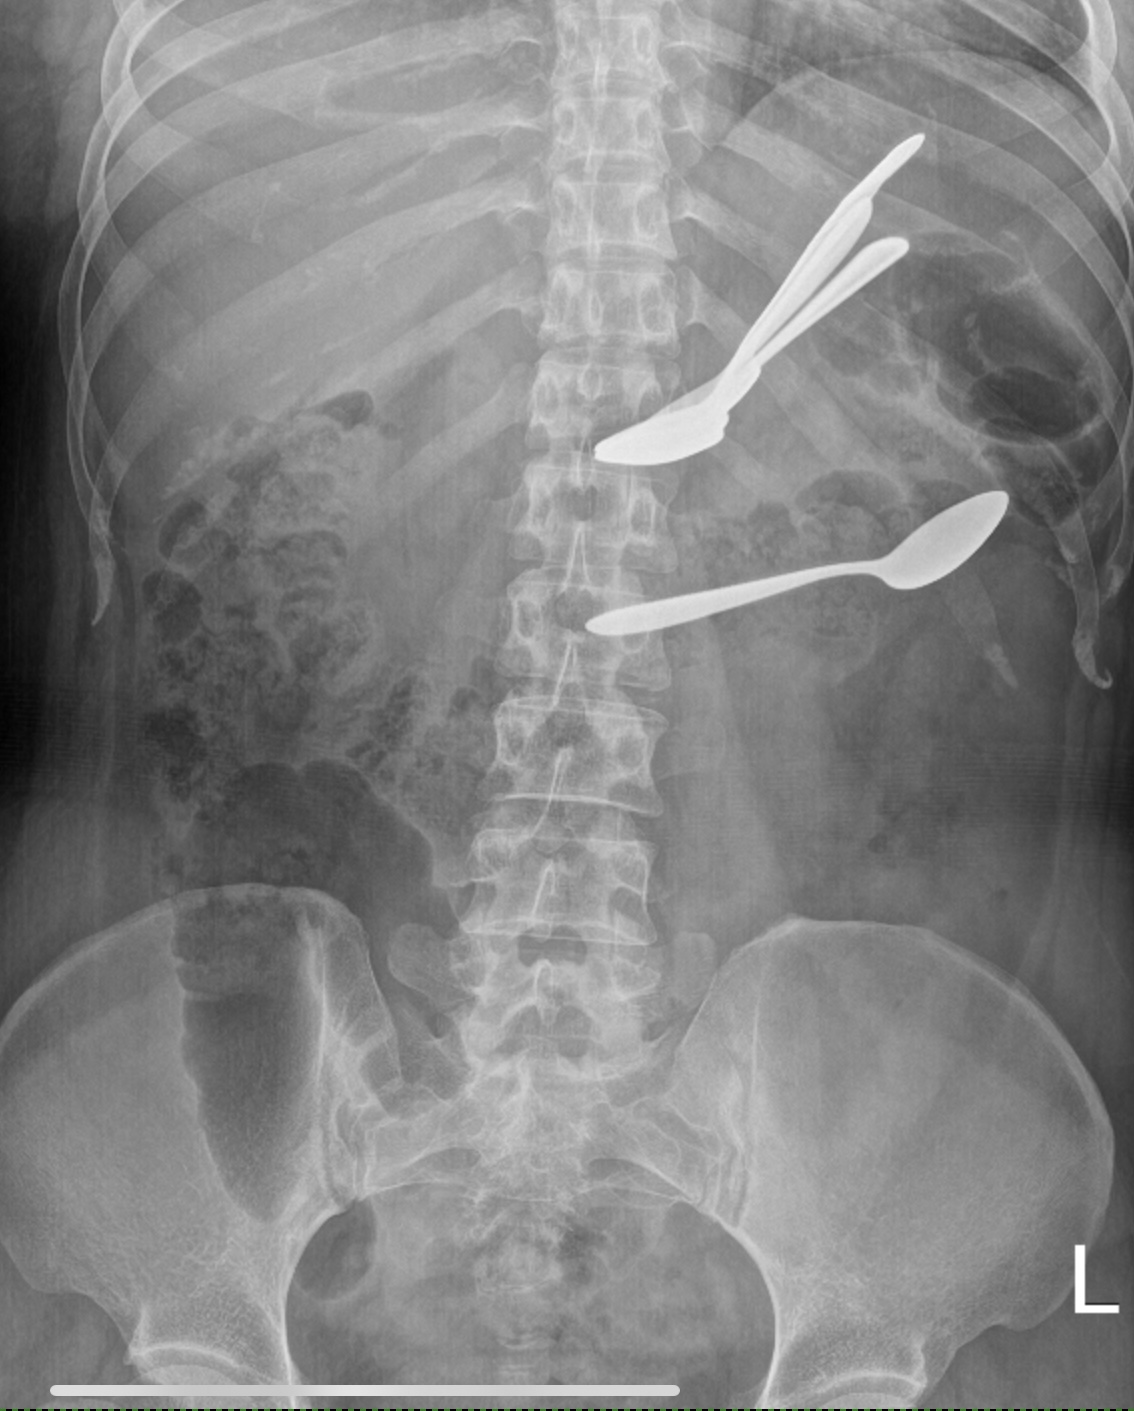

Foreign bodies in the stomach and transverse colon on abdominal X-ray

Foreign body ingestion is common among the pediatric population but is quite rare in adults, except in certain patient groups, where it is often successfully managed conservatively. We reported a case of foreign body ingestion in a 32-year-old psychiatric patient that was successfully managed using both endoscopic and non-operative methods. This case highlighted the importance of appropriate case selection for conservative or endoscopic management and discussed the criteria for operative intervention.